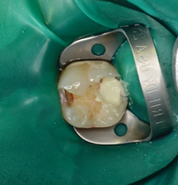

神経が露出(露髄)したのでMTAセメントで直接覆髄しました。 |

MTAセメントとは、1993年に米国で開発され 直接覆髄材に求められる理想的な性質として、非常に高い評価をうけています。 この後は、来週予後をみて修復処置を行う予定です。 |